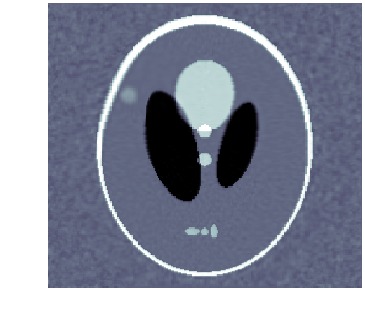

5.3 Consistent topology and inconsistent intensities

Here, topology of the template is consistent with that of the target, but intensities differ. The template, which is shown in fig. 2(a), is registered against tomographic data shown in fig. 2(c). The (unknown) target used to generate data is shown in fig. 2(b). Also, data has a noise level corresponding to a \acPSNR of and kernel size is , which should be compared to the size of the image domain . The final reconstruction is shown in fig. 2(h), which is to be compared against the target in fig. 2(b). Figure 2 also shows image, deformation and template trajectories.

We clearly see that metamorphosis based indirect registration can handle a template with wrong intensities. As a comparison, see fig. 1(c) for the corresponding \acLDDMM based indirect registration using the same template and data. Furthermore, the different trajectories also provides easy visual interpretation of the influence of geometric and intensity deformations.